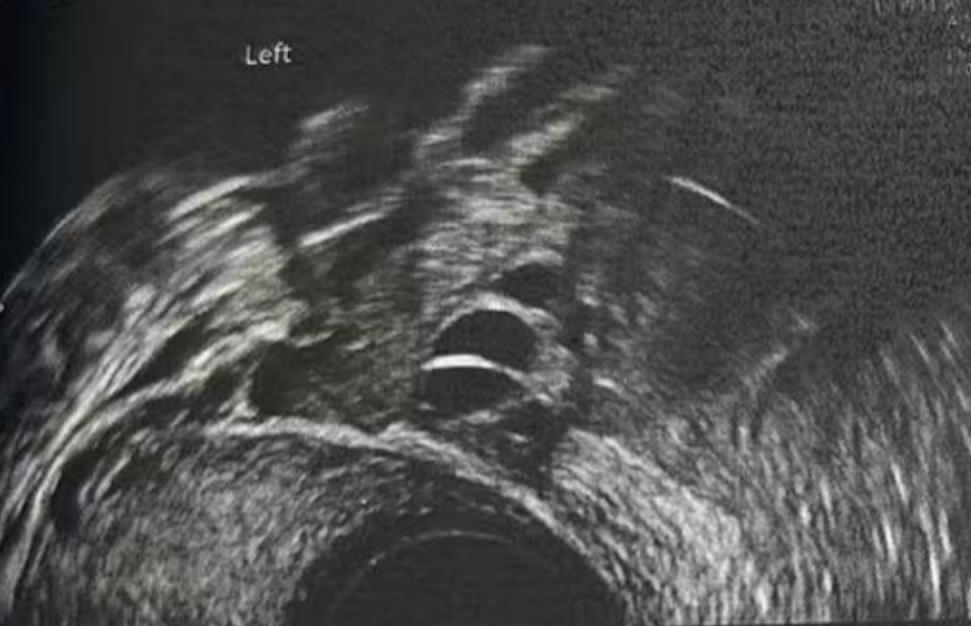

• 阴超检查:基础卵泡 6 颗

- 右侧卵泡 2 颗 (3-4mm)

- 左侧卵泡 4 颗 (3-5mm)

阴超检查:

- 右侧卵泡 2 颗

- 左侧卵泡 6 颗

促排第九天

- 右侧卵泡 2 颗 (10,20mm)

- 左侧卵泡 5 颗 (20,18,12,7,7mm)